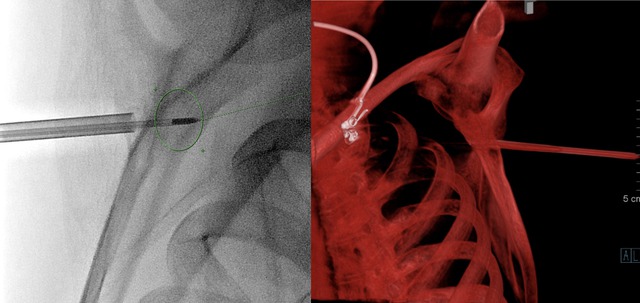

Tại Bệnh viện Đại học Y Hà Nội, bệnh nhân đã được thực hiện đốt sóng cao tần dưới hướng dẫn của hệ thống DSA. Chia sẻ về ca phẫu thuật, TS.BS Nguyễn Ngọc Cương cho biết: "Ê-kíp sử dụng kim chuyên dụng để định vị chính xác tổn thương, sau đó dùng nhiệt của sóng cao tần để triệt tiêu hoàn toàn khối u trong xương.

Phương pháp này giúp loại bỏ tổn thương mà không cần mổ hở, giảm tối đa đau đớn và rút ngắn thời gian hồi phục. Chỉ sau 1 ngày điều trị, bệnh nhân không còn cần thuốc giảm đau, chỉ cảm thấy hơi ê ẩm vùng vai khi vận động nhẹ. Sau hai tuần, mọi triệu chứng biến mất hoàn toàn, anh đã có thể trở lại sinh hoạt bình thường.